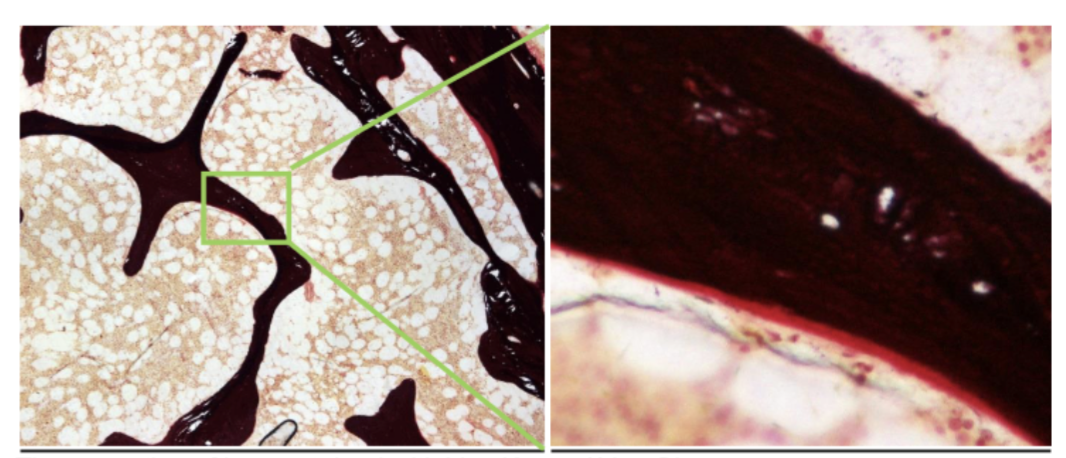

black staining in nephrons

PASM - methenamine

• silver/black - basement membrane